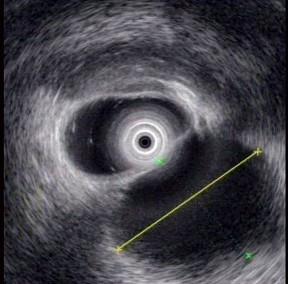

问题 男性,25岁。因急性胰腺炎住院1周,出院3周后仍有持续性上腹痛和背痛。查体无发热,在中上腹可触及一界限不清的包块,无压痛。血白细胞计数及分类正常,血清淀粉酶800苏氏单位。超声内镜如图中胰腺病变可能的诊断是 ( )

选项 A、胰腺囊腺癌 B、胰腺癌 C、胰腺真性囊肿 D、慢性胰腺炎 E、胰腺假性囊肿

答案 E